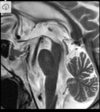

Esclerose mesial temporal

Observe a perda de volume, que indica atrofia e causa aumento secundário do corno temporal do ventrículo lateral.

O sinal alto no hipocampo reflete a gliose.